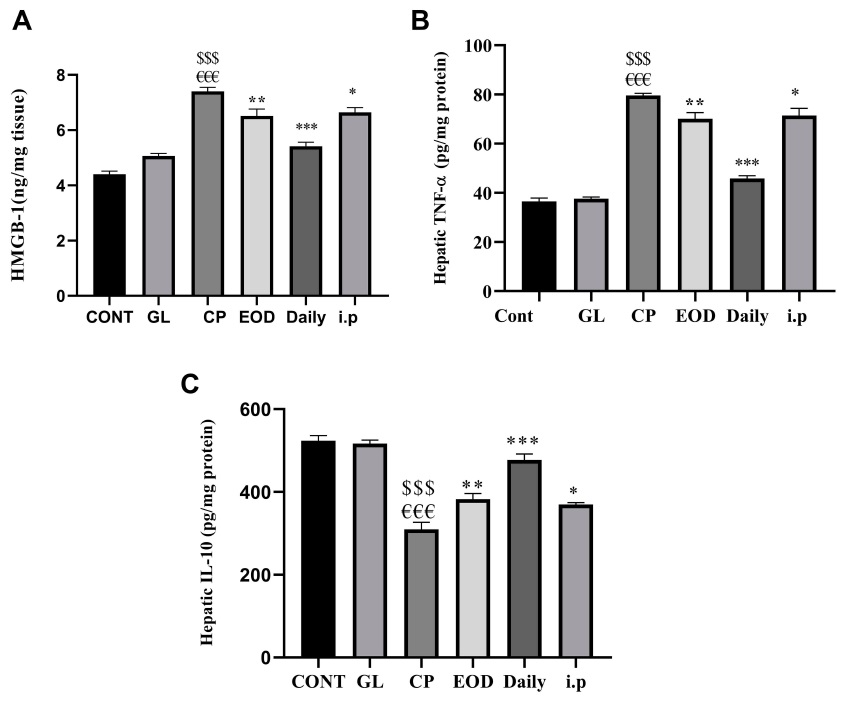

(3)Ganoderma lucidum enhances the anti-inflammatory ability of liver cells

Cisplatin threatens the survival of cells by damaging DNA and inducing a large number of free radicals; cells under pressure will turn on the master switch NF-kB that regulates the inflammation response, prompting cells to synthesize and release tumor necrosis factor (TNF-α) and other cytokines to activate the first wave of inflammatory reactions and sound the alarm for immunity.

Immediately afterwards, those cells killed by oxidative damage or inflammation will release another cytokine, HMGB-1, to activate more immune cells, triggering waves of inflammation.

Continuous inflammation will not only, in turn, intensify oxidative damage but also drive more cells to death, and even cause liver tissue to gradually develop fibrosis during the process of repeated inflammation and repair.

Fortunately, just like Ganoderma lucidum can reduce the oxidative damage caused by cisplatin, animal experiments also confirmed that the combined use of cisplatin and Ganoderma lucidum can inhibit the activation of the inflammation switch NF-kB, reduce the inflammation-promoting TNF-α and HMGB-1, and increase the anti-inflammatory cytokine IL-10 in the tissues of the liver at the same time (Figure 4).

Taken together, these effects not only inhibit inflammation but also reduce collagen deposition and prevent the progression of liver fibrosis (Figure 5).

Figure 4 Effects of cisplatin and Ganoderma lucidum on inflammation of liver tissue